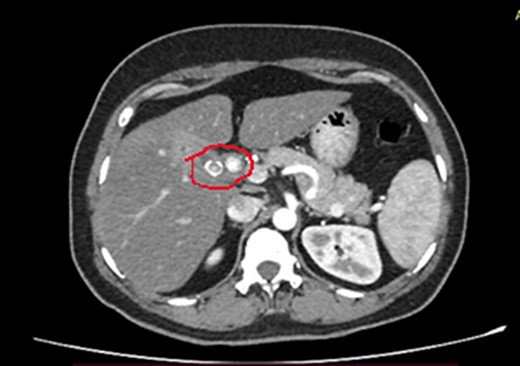

She has undergone a semi-elective ERCP in a semi-prone position, under sedation with propofol target-controlled infusion. Major papillae identified with side viewing endoscopy. Guidewire was inserted into CBD, and a cholangiogram was done. It showed dilated CBD up to 1.3 cm, mild dilated hepatic ducts, and a large radiolucent area in the distal CBD (around 1.5 cm). Sphincterotomy was done with a sphincterotome, and the ampulla was dilated up to 1.5 cm with a balloon dilator. Then, a balloon retrieval was attempted and failed, probably due to a stone sticking to the CBD wall. Then, a mechanical lithotripter was used to break the stone, but it failed, damaging the instrument. During the procedure, her oxygen saturation dropped to 75–80%, and she developed surgical emphysema in the face, neck, and upper chest region. In addition, she developed abdominal distention as well. Immediately, she underwent CBD stenting with a 12-cm, 10 French Gauge double pigtail biliary stent and changed her position to supine. Then, she was intubated with rapid sequence induction, and a nasogastric tube was inserted and transferred to the surgical intensive care unit. Post-ERCP, non-contrast computed tomography (NCCT) of the abdomen and chest showed extensive pneumo-peritoneum and retroperitoneal gas with subcutaneous emphysema (Figs 2 and 3). There was no evidence of air leakage on NCCT and no clinical features of peritonitis on subsequent days. So she was managed non-surgically with nasogastric tube (NG), nil by mouth, intravenous fluids with intravenous antibiotics. Clear fluid was started after 24 hours slowly via NG.

Post-ERCP NCCT abdomen shows pneumo-retroperitoneum (red arrow).